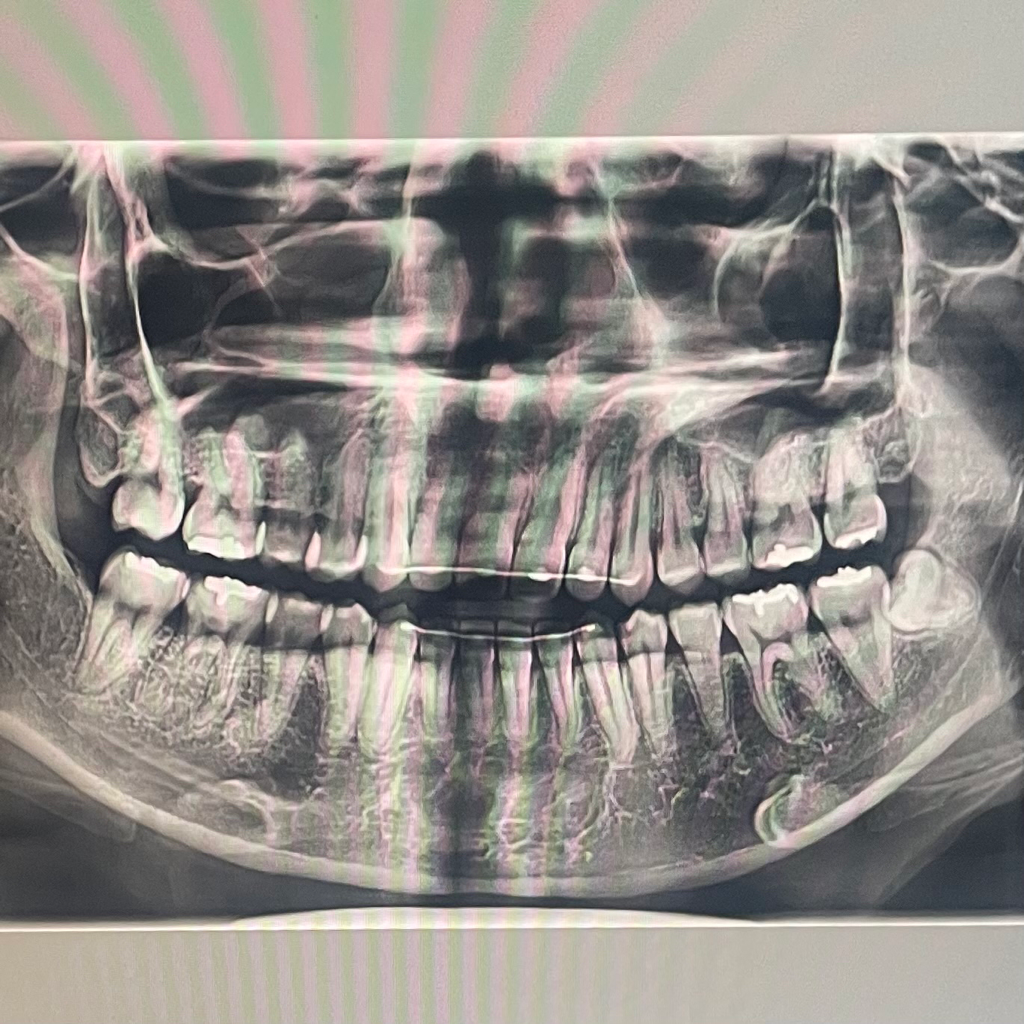

사랑니가 나와봐야 정확하겠지만, 아마 각도상 그대로 누워서 날 것 같습니다. 그러면 뽑으셔야 합니다

현재 상태에서는 그대로 두게 되면 사랑니와 어금니 사이에 음식물이 많이 끼어 염증 및 충치가 생길 가능성이 매우 높습니다. 따라서 가급적이면 미리 발치를 해주는 것이 좋습니다. 지금은 증상이 없어 별다른 문제를 일으키기 않지만 시간이 지나면 문제가 생길 가능성이 매우 높아 보입니다.

지금상태에서는 크게 문제가 없다면 일단 지켜보시는게 좋을것같습니다. 하지만, 그쪽에 염증이 생기거나 붓는다면 발치를 하시는게 좋습니다.

매복되어 있고 다른 치아에 문제를 발생시.킬가능성이 없다면 발치.하지 않아도 됩니다.

자라나면 웬만하면 뽑으시는 것이 좋으며 매복사랑니인 경우 선택적인 사항이지만 그래도 젊을때 뽑는것이 발치의 난이도가 쉽습니다.

인접치아의 치근흡수, 인접치의 이동, 악궁의 공간소실 등을 유발할수있기 때문에 발치 하는것이 좋습니다.